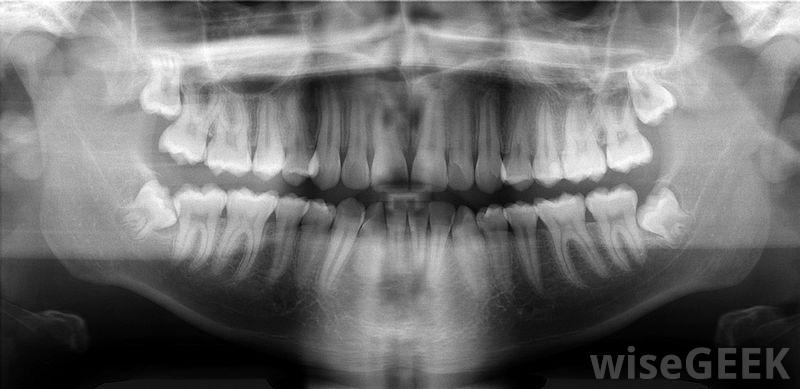

水動力學理論解釋了為什么有些人的牙齒會對冷熱等刺激產生反應。這一觀點是基于牙科專家在對病人進行檢查時觀察到的結果,水動力學理論強調了琺瑯質和牙骨質的物質在防止牙齒變得敏感方面的重要性,它還強調了暴露在牙齒上的一種叫做牙本質的物質是如何導致敏感的,這種敏感性通常是短暫的,需要使用某些產品來解決這個問題牙骨質覆蓋在牙根表面,只有通過X光才能看到。牙科領域的專家使用流體力學強調琺瑯質和牙骨質防止牙齒變得過于敏感的理論。牙本質是牙齒上琺瑯質或牙骨質所在的部分。琺瑯質是最堅硬的牙齒材料,覆蓋了牙冠,牙齒在口腔中可見的部分。牙骨質覆蓋著牙根的表面,牙骨質被嵌入其中在骨中。如果牙本質沒有被這些材料覆蓋,并且由于牙齒缺陷而暴露在外,患者會感到敏感。通常與牙齒敏感相關的疼痛很唐突這一保健理念的另一個方面是,小管構成牙本質,從而對個人感覺到的牙齒敏感性產生影響。當有人對牙齒造成磨損時,牙齒表面和周圍牙齦的磨損會暴露牙本質小管。如果牙醫使用空氣用注射器沖洗牙齒表面,這會迫使液體進入牙小管。同時,吃酸的食物會導致液體流出小管。根據流體力學理論,牙本質小管內液體的不斷來回移動和牙本質液體中壓力的變化會導致牙齒敏感根據流體力學理論,牙釉質和牙骨質可以保護牙齒不致對冷熱過于敏感與牙齒敏感相關的疼痛通常是非常突然的。根據流體力學理論,一個人在他或她的牙齒上感覺到的感覺,通常只在有空氣沖擊等刺激時才會出現。一旦敏感的原因被消除,疼痛就有減輕的趨勢牙本質是牙齒上覆蓋琺瑯質或牙骨質的部分使用針對牙痛的產品和程序是針對這類口腔問題的一種常見方法。例如,公司生產專為患牙齒敏感癥的人設計的牙膏。此外,研究表明,激光治療有助于針對水動力學理論所強調的不適牙感。琺瑯質是最堅硬的牙齒材料,是牙齒可見的部分。